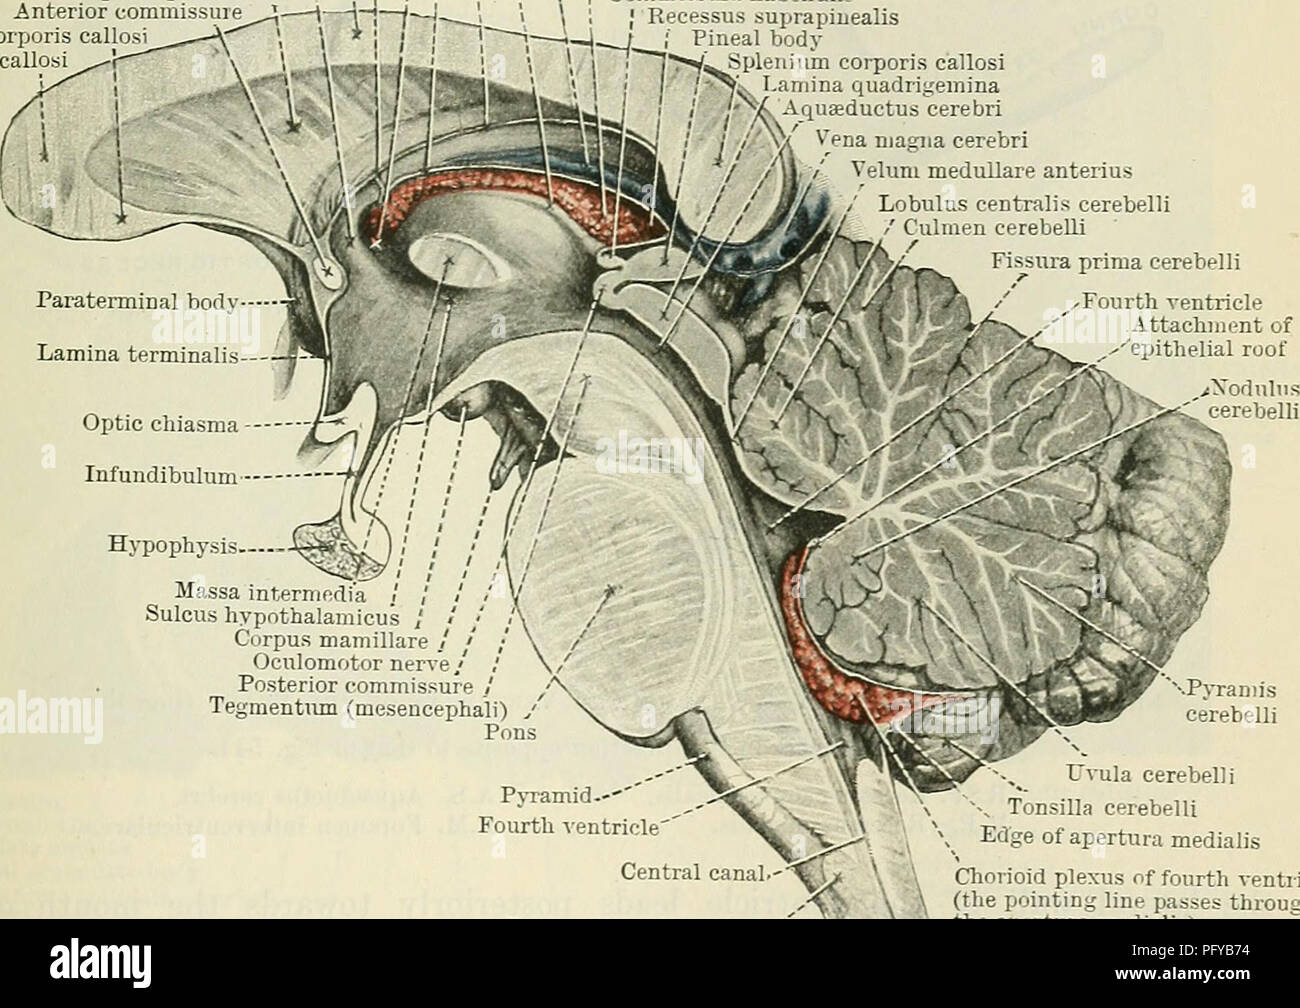

RMPFYB74–. Cunninghams Lehrbuch der Anatomie. Anatomie. PAETS abgeleitet aus dem ZWISCHENHIRN. 617 davon, welche das Aquädukt umgibt, ist direkt kontinuierlich mit der grauen Substanz der substantia perforata posterior und Tuber cinereum, und auf diese Weise kommt es zu der Oberfläche in der Unterseite des Gehirns. Die optic Chiasma kreuzen den Boden vor und markiert die Stelle, wo der Letzteren stetig mit der anterioren Wand des Hohlraums wird. Die vordere Wand des dritten Ventrikels wird durch die Lamina terruinalis, die sich nach oben erstreckt sich von der Optic chiasma gebildet. Die anteriore com-missure, wie es kreuzt von einem

RM2AWFNN9–Menschliche Anatomie, einschließlich Struktur und Entwicklung und praktische Überlegungen d in einem sagittalen mesialen Abschnitt (Abb. 910) wird jede dieser Teilungen als mit einem Teil des Systems der Kommunikation von Räumen verwandt angesehen, die als die dritten Ventrikel des Lateralands, der Aquädukt von Sylvius und der vierte Ventrikel die oben genannten Gehirnhemisphären ausdehnen. Durch den Hirnstamm und unter dem Kleinhirn bis zum zentralen Kanal des Rückenmarks. Da die lateralen Ventrikel zwei innumerieren, ist die Theirstellung im Zusammenhang mit den Gehirnhemisphären, in denen sie liegen, lateral zum m